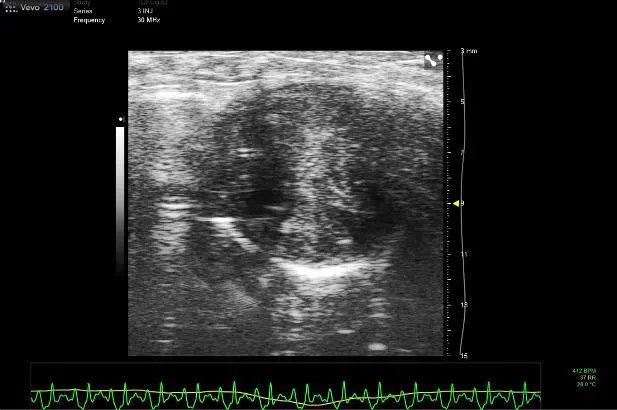

新加坡国家心脏中心与杜克—新加坡国立大学医学院的研究员联手展开了这方面的探索。他们把多巴酚丁胺(dobutamine)注入蝙蝠体内,评估它们在心脏受压时的泵血功能。多巴酚丁胺是一种可增加心脏压力的药物,用于增强心肌收缩力和心排血量,可治疗心力衰竭。

研究显示,蝙蝠的心脏在受压时,泵血能力更强,表明了蝙蝠的心脏系统强壮,可以抵抗压力。

新加坡国家心脏研究所主任侯可达(Derek Hausenloy)教授接受《联合早报》访问时说,蝙蝠飞行时的心跳可从每分钟跳100次,增至1000次;换言之,蝙蝠的心脏可以在承受高压时维持功能,这为一直在寻找预防心力衰竭新疗法的研究员提供了方向。